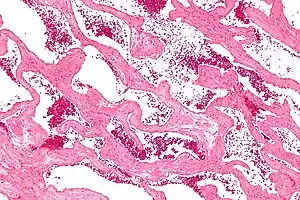

Micrograph of a cavernous liver hemangioma. H&E stain.

Liver cavernous hemangioma

Cavernous hemangiomas are the most common benign tumors of the liver.[5] Usually one tumor exists, but multiple lesions can occur in the left or right lobe of the liver in 40% of patients.[6] Their sizes can range from a few millimeters to 20 centimetres. Those over 5 cm are often referred to as giant hemangiomas.[6]